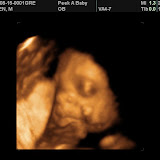

28 Weeks

We are now 28 weeks along and baby is so very active all day long! Yesterday we went to get 3D ultrasound pictures to get a better look at #2. Check out the web album below. It's amazing how much more excited we are now that we've seen his face and all his expressions.

| Baby 2 3D Ultrasound |